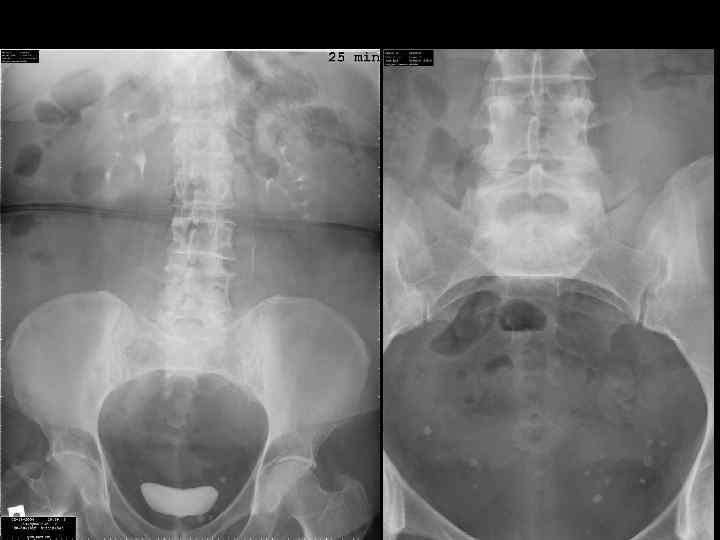

норма